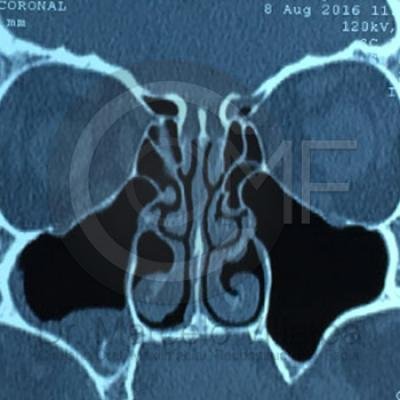

Comunicación en Seno Maxilar

Comunicacion Seno Maxilar 16